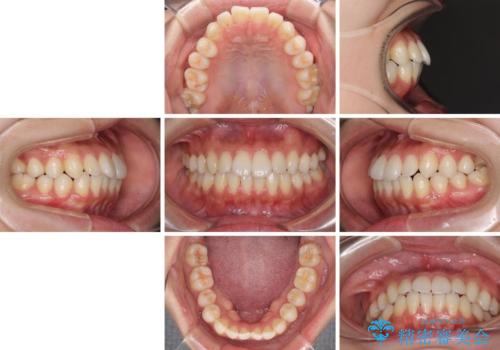

- 下唇に上の前歯が当たることを気にして来院された患者様です。

上顎の親知らずを抜去し、歯列全体を後方に移動させるとともに、IPR(歯と歯の間を削る)を行うことで口元の閉じにくさを改善していくこととしました。

咬合力が強く、マウスピースを介した咬み込みが顕著であったため、奥歯の咬みにくさやIPRのスペースが改善しにくく、治療期間が思った以上にかかってしまいました。